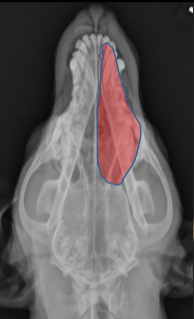

ID

Maxilla

Zygomatic Bone

Orbital Margin

Coronoid Process of Mandible

ID Radiographic View

Open Mouth VD view of Nasal Cavity